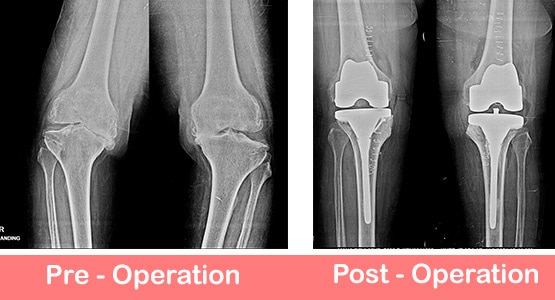

I consulted Dr. Joel Prasad for my mother’s arthritis, and he recommended a Robotic Knee Replacement. He took the time t...

Read More